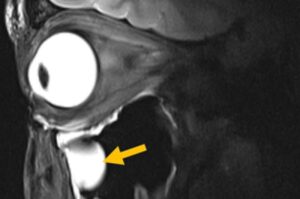

Magnetic resonance imaging (MRI) is one of medicine’s most powerful diagnostic tools. But certain tissues deep inside the body—including brain regions and delicate structures of the eye and orbit that are of particular relevance for ophthalmology—are difficult to image clearly. The problem is not the scanner itself, but the hardware that sends and receives radio signals.